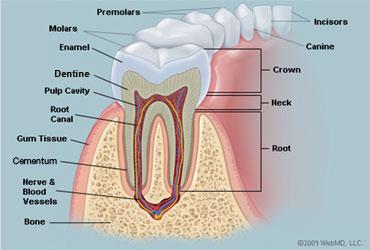

Crown

20

Neck

21

Root

22

Alveoli

23

Gingiva

24

Enamel

25

Dentin

26

Cementum